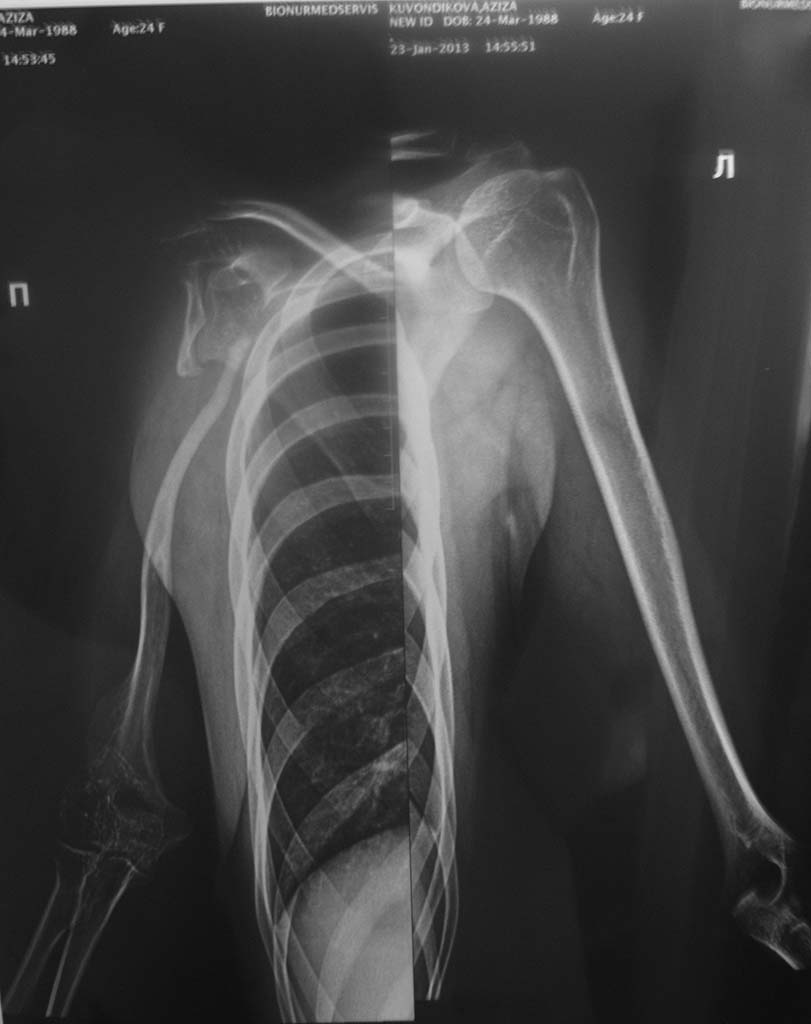

Поступила больная А. 24 года. Из анамнеза болеет с детство. Оперирована

в детстве. Резекция головки плечевой кости и Артродез плечевого сустава

с перемещением ауто трансплантатом . 2 месяц назад упала на

оперированную конечность : При осмотре у нас. Боль, Патологическая

подвижность в в/3 правого плеча . На рентгеновские снимки атрофия правой

плечевой кости. Что можно делать в таких случаях? Спасибо.